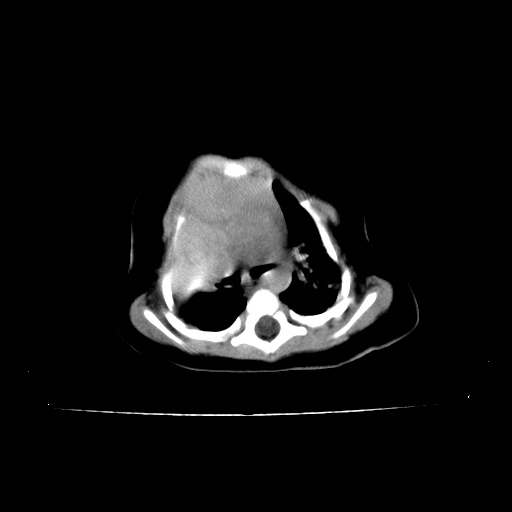

以下是引用影像之路在2009-5-8 15:46:00的发言:[br]1)胸廓畸形。2)考虑两肺感染性病变,并右肺上中叶肺不张;建议抗炎治疗后复查。3)胸腺肥大。4)前上中纵隔占位性病变待排;建议追踪复查。

以下是引用余辉在2009-5-8 8:44:00的发言:[br]鸡胸,胸腺肥大,双肺感染性病变,结合病史支原体肺炎可能性大